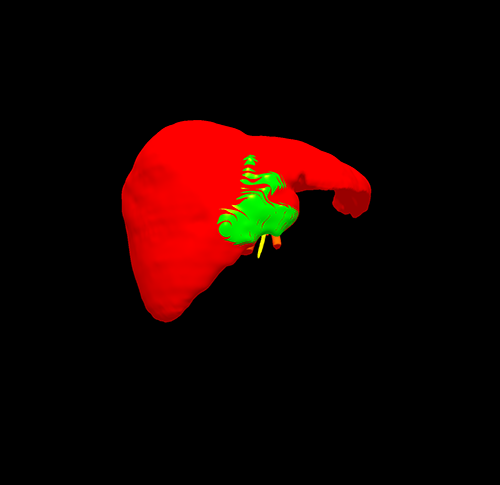

左肝癌并胆管癌栓---左半肝切除、胆管癌栓取出术